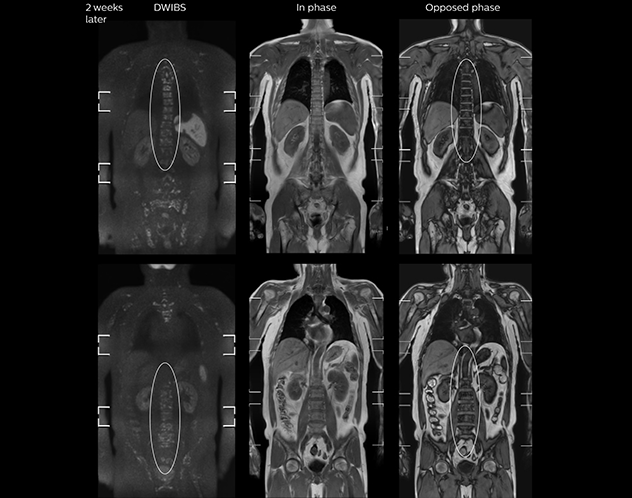

“When we limited the scan coverage to the area from neck to femur, we could fit more clinical information in approximately the same scan time. So, we added coronal mDIXON, sagittal T1-weighted, and sagittal STIR sequences to our examination, instead of performing only axial DWIBS and coronal single-shot TSE scans.” The single shot T2-weighted TSE images are used for morphology and compared to DWIBS images to identify T2 shine-through. Sagittal STIR images are used in patients with inflammation or bone metastasis.

“mDIXON FFE allows us to quickly get information we need to assess the presence of fat. That gives us more information when we need to diagnose bone lesions, and when we are asked to judge fat-containing lesions such as hepatocellular or renal carcinoma,” Dr. Nobusawa says. “The mDIXON fat images can help us to differentiate fatty bone marrow from bone lesions. This is especially useful in elderly people, who tend to have fattier bone marrow. The water images provide a high signal-to-noise ratio in the intestinal canal, which is valuable for visualizing lesions in the colon,” he says.

Kawasaki Sawai Hospital’s whole body protocol also includes an mDIXON FFE sequence. Because mDIXON provides images for four contrast types – water only, fat only, in-phase and out-of-phase – from a single acquisition, it is useful in many ways.

“In-phase and out-phase sagittal T1-weighted FFE images help us to visualize and further characterize bone lesions such as metastasis and bone-marrow hyperplasia that have high signal on DWI. These images are also used throughout radiotherapy, to monitor changes in the fatty bone marrow.”